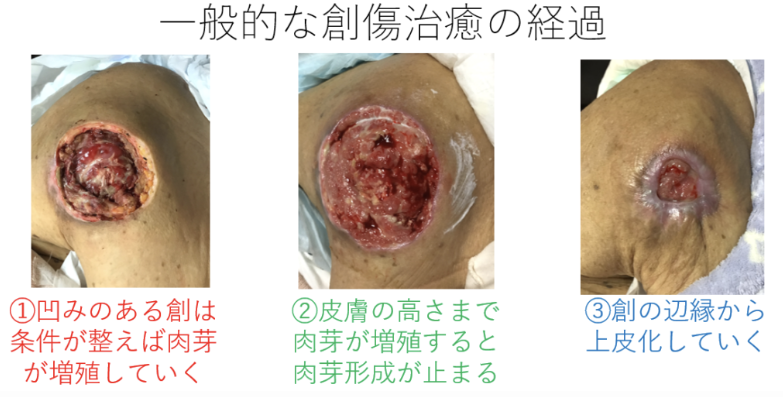

褥瘡の「創縁」「創面」の性状を把握しよう 2ページ目 :日経DI。

⑤深い褥瘡攻略の道標 ”TIME+α”のE 創部辺縁の段差 :難関攻略!褥瘡ポケットを治す秘策とは!? -皮膚科専門医が伝授!医療従事者のための高齢者皮膚トラブル対策講座。

傷の治り方 - 治り方から傷あと治療まで - 傷についてもっと詳しく創傷治癒センタ。